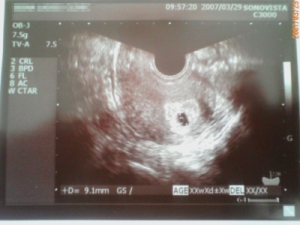

今日、病院で胎のうを確認して来ました。ドキドキしながら診察台から覗いていると、空洞が1つ見えました。(ほかに表現が出来ない・・・)もしかしたら、来週もうひとつ見えるかもしれず、とりあえず1つとのことでした。現在、5週3日目出産予定日、11月23日初期説明をうけました。3ヶ月まで流産の可能性が高いので、無理はしないで下さいとの事でした。来週の心拍確認まで、ドキドキです。そして、今まで、不妊センターだったのが、明日からの注射は産婦人科になります。注射と飲み薬がまだ続行で、2週間分でました。私のおしりちゃん、左側にしこりが出来、3日連続右に打っているのですがなんとか、だましだまし?頑張っています。医療費23日 1,480円24日 1,830円25日 2,030円26日 9,600円